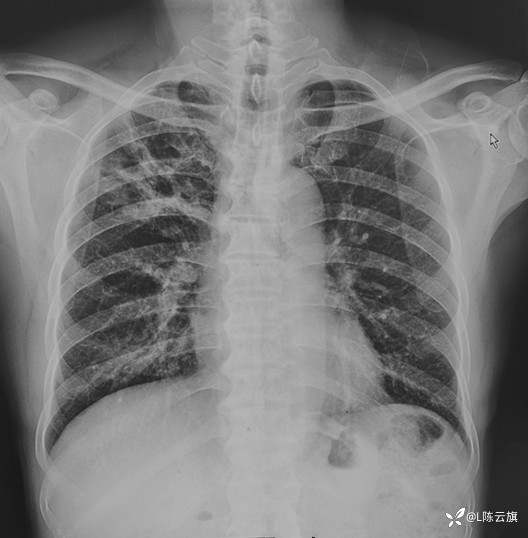

1、患者男,现在59岁,胸部正位片(一)是患者6年前以精神病收住院患者所照的胸片,当时的病史已不详;胸部正侧位片(二三)是现在新入院的照片,没有明确的呼吸道症状和病史!期间是否有过照片已查不到,但患者家属说未作过真正的系统治疗!

2、根据两次的胸片表现。你如何诊断?分别是什么基本病变?下周发布病变描述和CT图片!

3、结合CT所见结论是:①.6年前胸片(一)所见是 渗出性病变--平片表现 右上中肺野大片状密度不均阴影,两下肺野小量小斑点片状影;②.现在的胸片(二三)所见是 右上肺野较多量粗条索状密影,大部分边缘清楚,左下肺野小片阴影已消失,右下肺纹理明显增粗增强;③.CT片证实右上肺病变为纤维性病变,但仍有小部分边缘欠清;④.最后诊断为:右上肺结核大部分纤维硬结。

胸片(二)